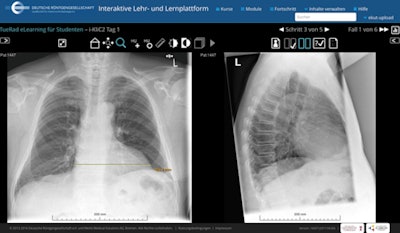

TueRad e-learning on the DRG platform. All images courtesy of the DRG.

They can work on case studies with all the functionality of a PACS workstation, and view high-resolution images with no clues or markings, as you would see in most textbooks. Radiology is much more fun if you solve problems yourself. Another advantage is that we can explore specific course subjects in more depth, and repeat them if necessary.